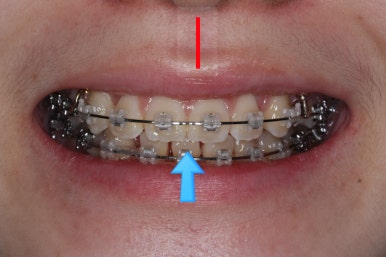

다만, 웃거나 말할 때 드러나는 치열을 보면 코~인중까지 이어지는 얼굴의 중앙선에 대해서 윗니의 중앙이 우측으로 쏠려 있는 것을 볼 수 있었습니다.

교정치료를 하게 되면 분명 이 부분을 보완해야 했습니다.

부산교정 키다리아저씨치과에 처음 내원하셨을 때의 입안 모습입니다.

윗니가 삐뚤어져 있고, 아래앞니 사이에는 틈이 듬성듬성 보입니다.

아랫니를 살펴보면 화살표 표시를 해둔 송곳니~송곳니 사이에 치아가 1개 모자랍니다. 원래는 4개의 앞니가 있어야 하는데, 3개 밖에 없었습니다. 이런 결손치아의 경우는 다음과 같은 문제가 생깁니다.